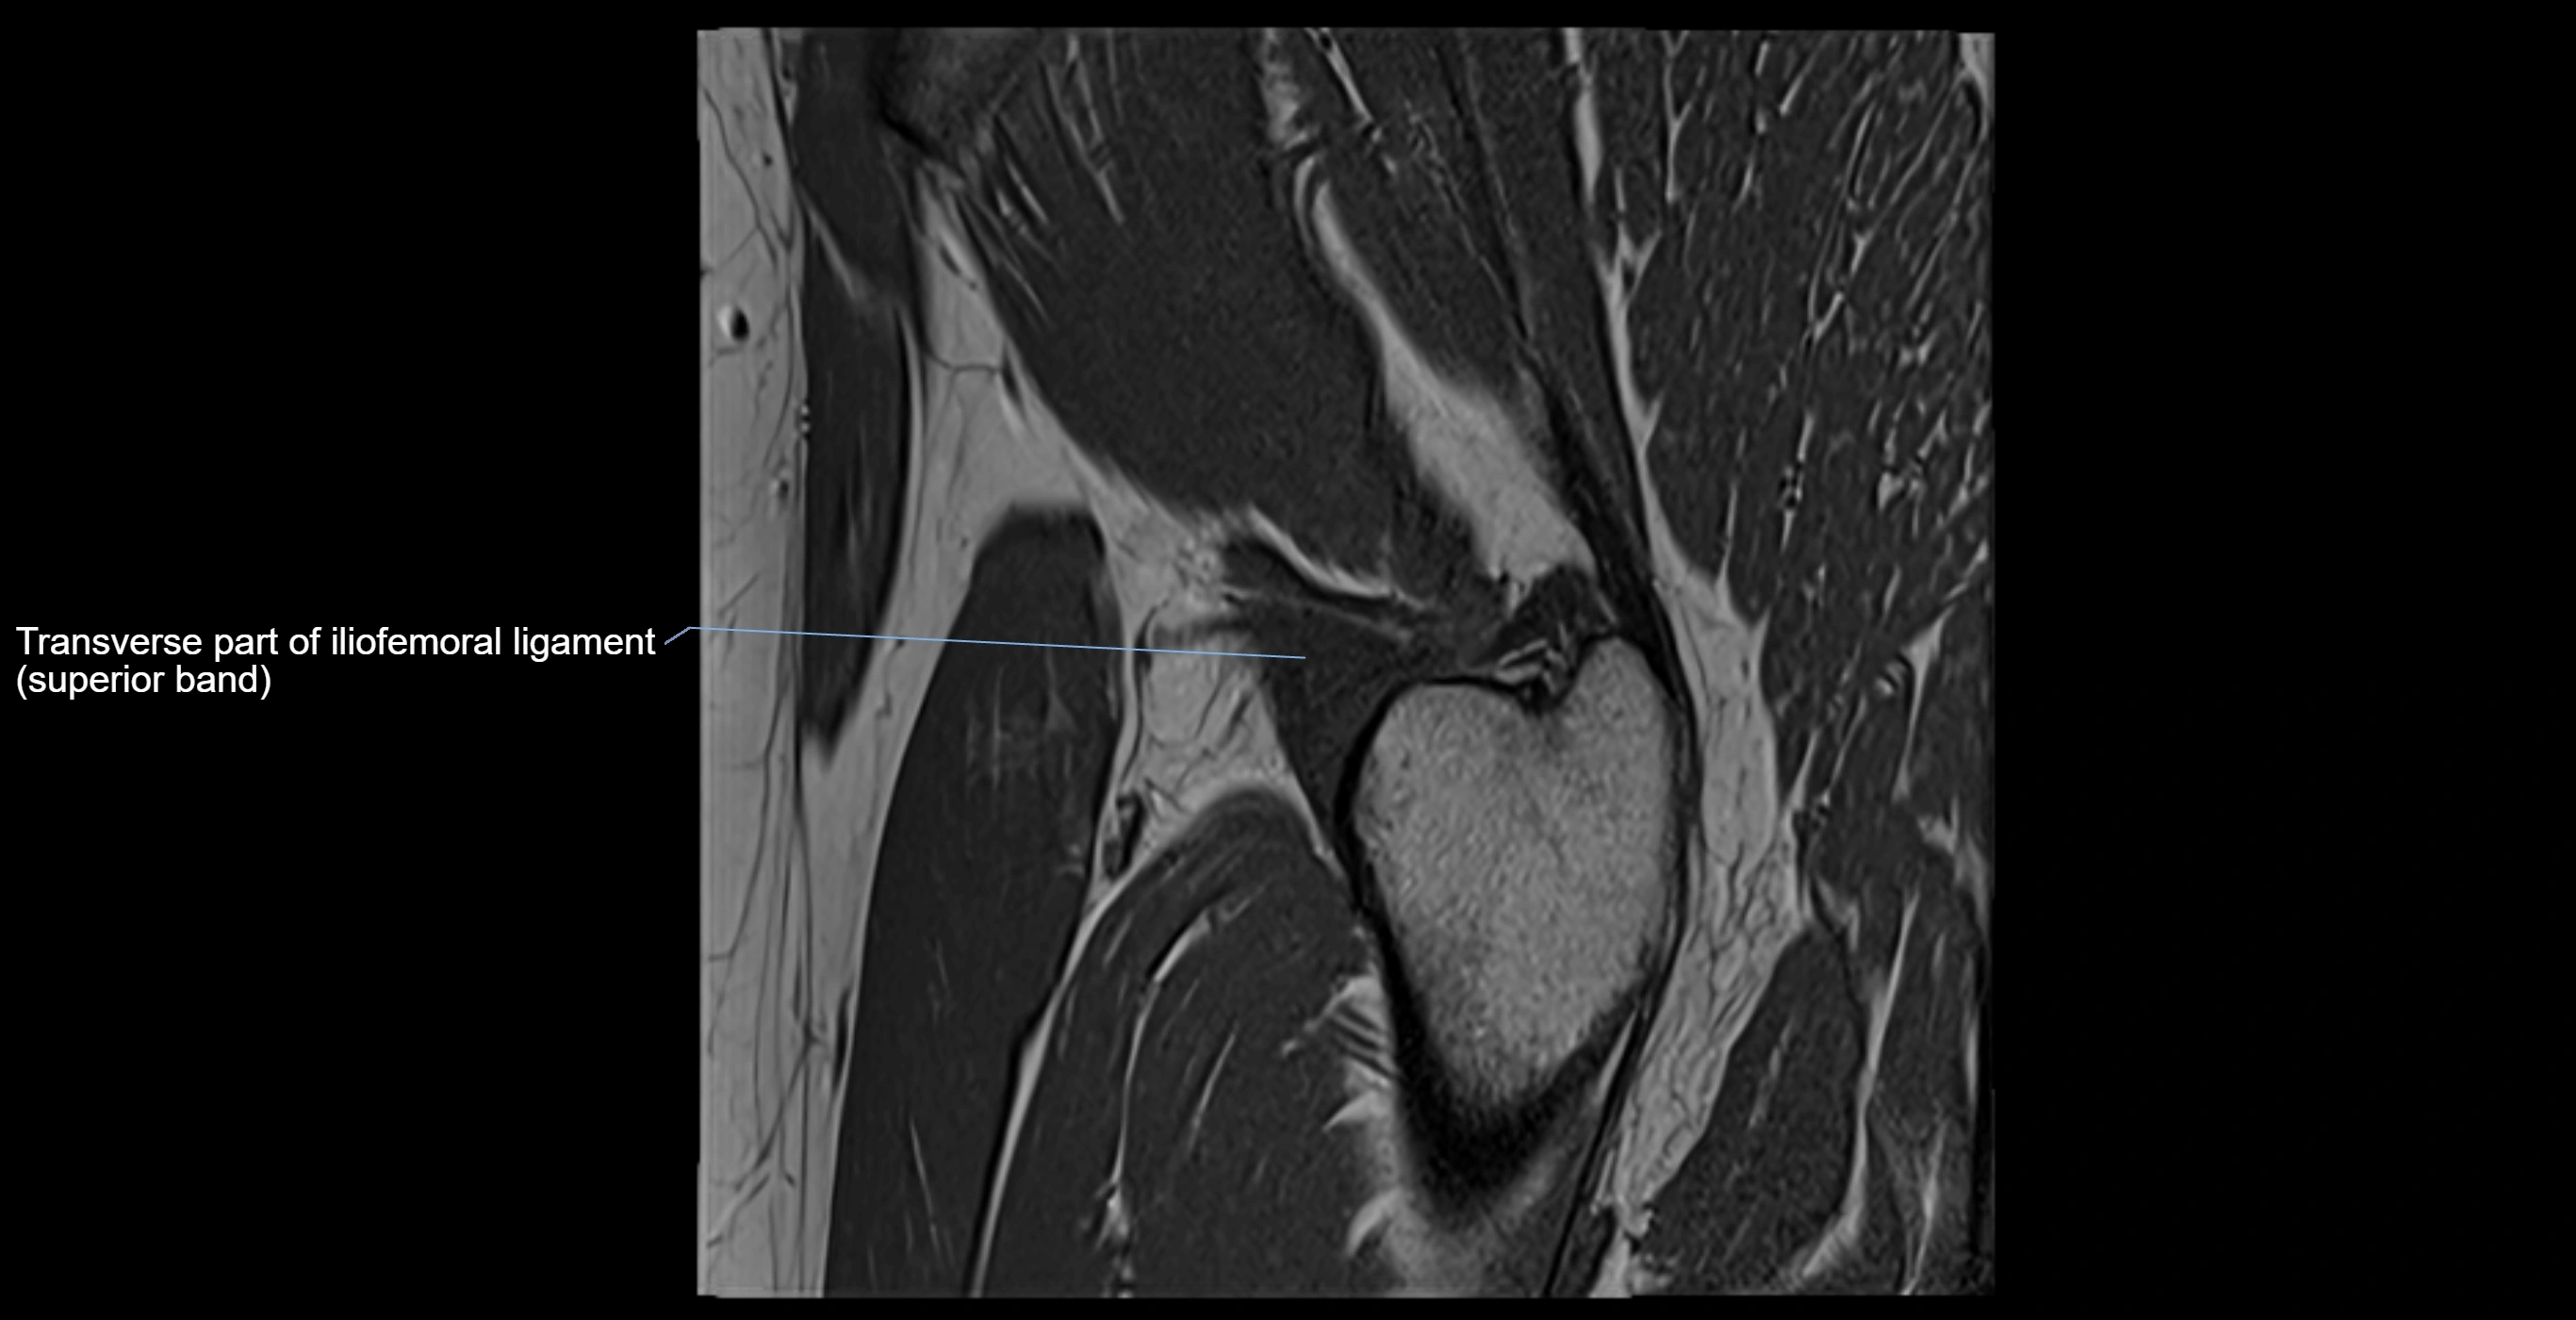

MRI image

image

MRI Appearance

T1-weighted images:

• Labrum: low signal intensity (dark)

• Surrounded by intermediate signal joint fluid (bright on arthrogram)

• Tears: linear or focal areas of intermediate-to-high signal interrupting labral continuity

T2-weighted images:

• Joint fluid: bright, making labral tears visible as fluid extending into or around labrum